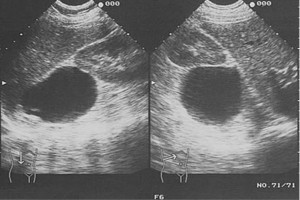

Diplomados en Ultrasonografía